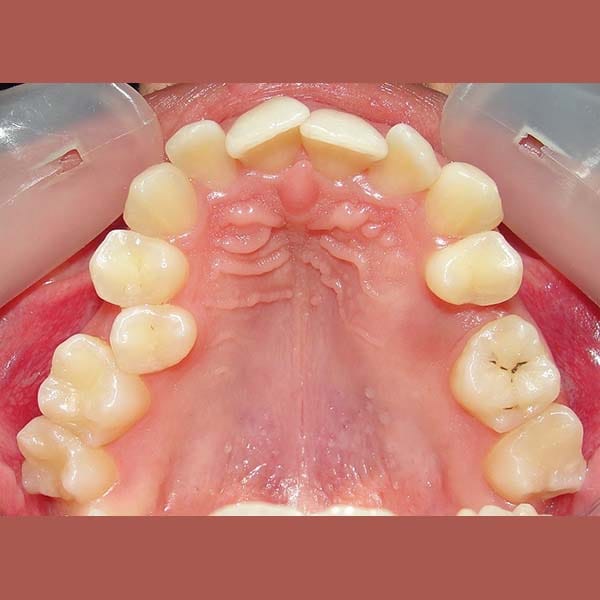

BEFORE

- This young woman suffered from an upper jaw stenosis, crowded teeth, and the absence of one of the upper molars.